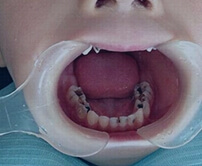

Root Canal Procedure Breakdown

Vickong Dental never abandons any diseased tooth.

Shenzhen root canal treatment overview

Patient Diagnosis

Endodontist confirms pulp infection via CT and X‑ray before proceeding.

Canal Preparation and Disinfection

Open pulp chamber, remove necrotic tissue, then disinfect canals with medicaments.

Canal Filling

Place medicament for 3–5 days to test pain relief, then complete canal filling if stable.

Crown Preparation and Sealing

Seal pulp and prepare a crown to protect the treated tooth.

Tooth Protection

Restore with porcelain crown or inlay to protect and preserve the tooth.